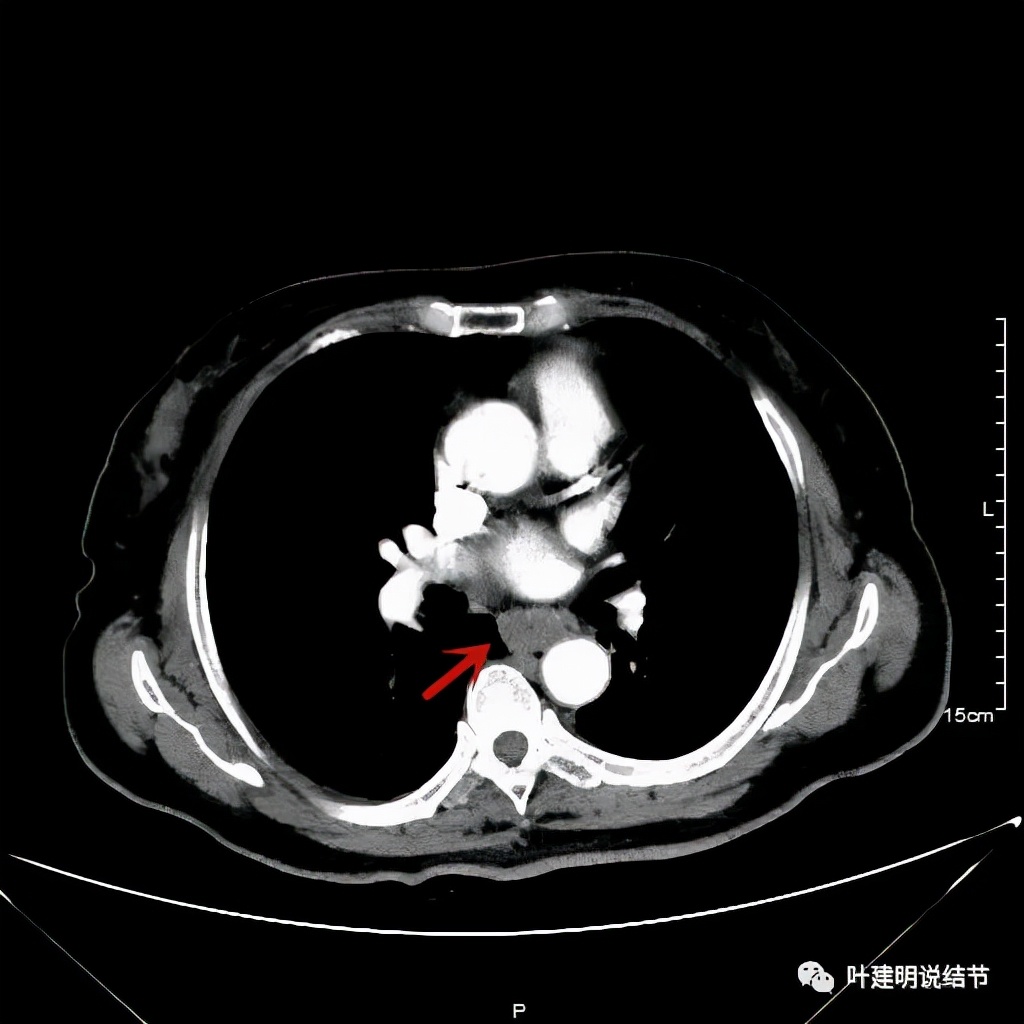

她是食管中分化鳞癌,但有腹部广泛的占位性病变,当初还以为是淋巴瘤,因为我们了几乎没有见过食管癌这种转移样子的。予以的治疗方案是“特瑞普利单抗+多西他赛+卡铂”免疫加化疗3次,后因患者不愿意继续化疗,仅予以特瑞普利单抗单药维持。我们再来看她刚发现时的胸部CT以及腹部CT增强的情况:

其实胸部CT示食管的病变感觉并不厉害,外侵或纵隔内转移均不明显,但其腹部的CT让人大吃一惊!

上图是初发现时的CT影像报告,其他CT图像上红色箭头所指范围内都是肿瘤,整合成团,挤压血管以及正常器官结构。你有见过原发灶这么不显眼,而腹部转移灶这么厉害的食管癌吗?但经过穿刺证实是转移性鳞癌,结合病史考虑是食管癌转移。手术自然是不可能了根治了,放疗也不合适,经过MDT并与患方充分沟通,依据食管癌治疗指南: